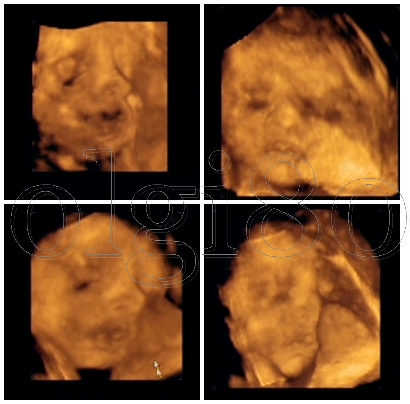

KépKép

Gyönyörű képek! :lol:

Leo: Ezek a képek? Tiszta Amerika :-) Gyönyörű kislány szuper minőségben. Gratulálok :P